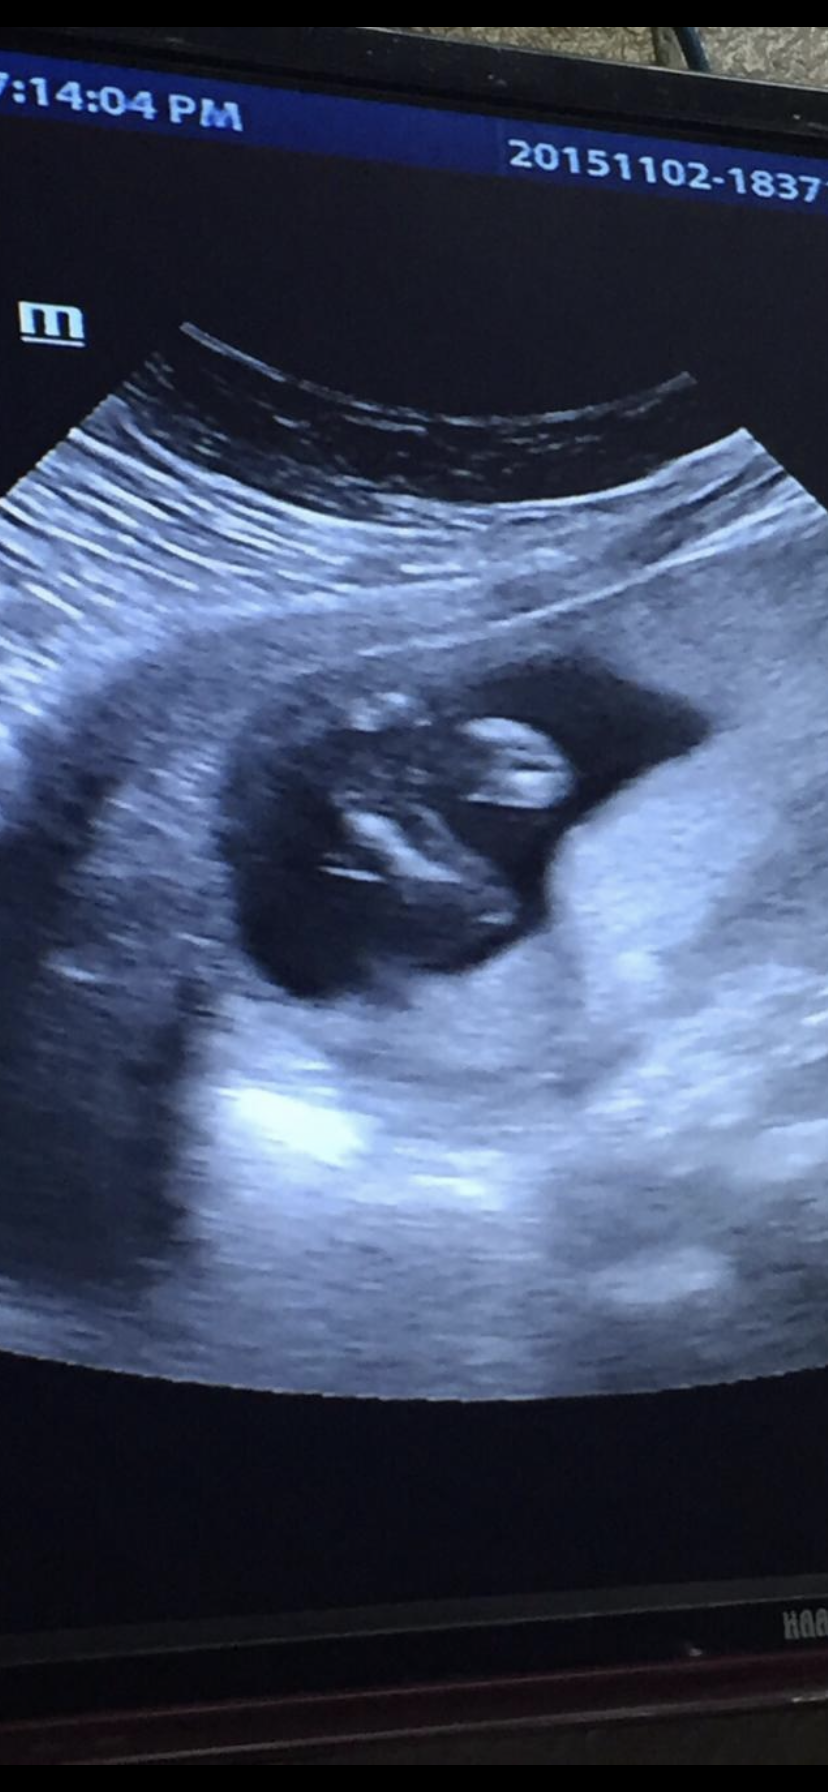

تقول خطوط زي اليساوي بنت و٣نقط ولد بالاسابيع ال١٥و ١٤

اي انا ببناتي اشوف الثللث خطرط بوريكم سونار قبل قديم لبنتي

هينا خطين زي اليساوي

وانا زي البنات اللي اعرفه ثلاث خطوط بنت والولد يكون واضح زي المثلث تقريبا

بس تقصد فالبدايه يكون ثلاث نقط بداية تكون العضو الذكري